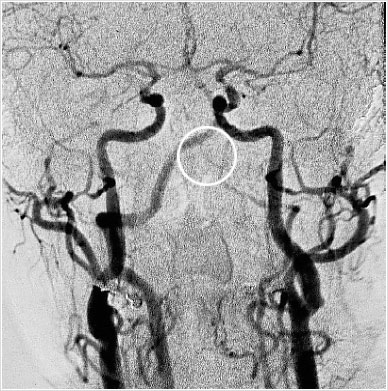

En la imagen de la circulación intracraneana (Fig 3 c, visión antero-posterior) se ve claramente la hipoplasia del segmento V4 de la vertebral izquierda.

Circulación intracraneana.